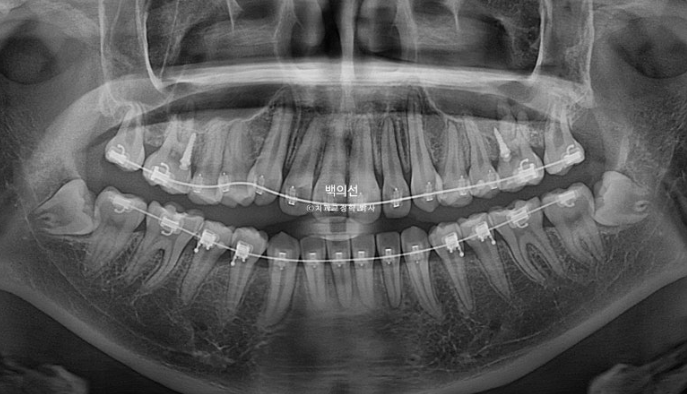

23.05~25.07

파란화살표는 사랑니입니다.

인비절라인으로 치료를 시도했던 기간은 1년 3개월(그중에 7개월은 장기 미내원), 클리피씨 장치를 붙여 치료한 기간은 11개월 입니다.

2년 2개월간 치근흡수는 없으며 치근평행도는 좋습니다.

특히 송곳니 덧니 쪽으로 쓰러져 있던 송곳니와 작은어금니 뿌리 치축 개선이 눈에 띕니다.